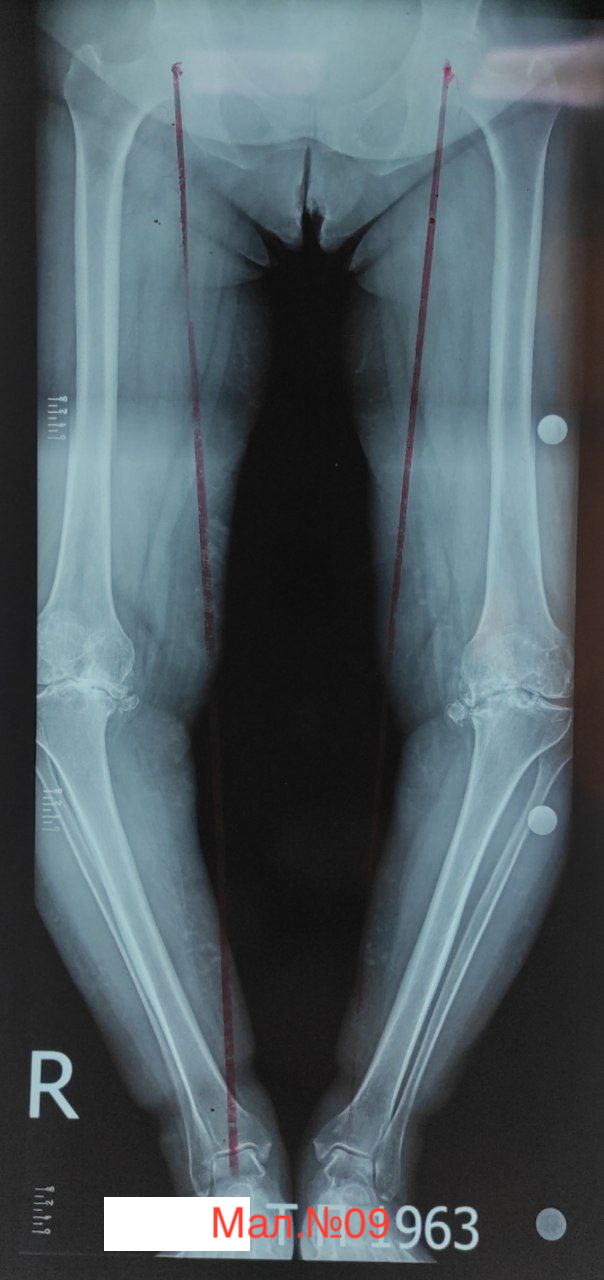

photo_2023-12-13 17.11.32